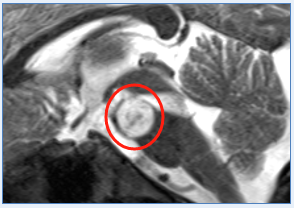

3. “一台手术,双入路”精妙手术创造15年生存希望

45岁的张先生突然遭遇剧烈头痛、喷射状呕吐,很快陷入意识模糊——这是颅内压急剧升高的危险信号!医生立即为他实施神经内镜下脑室造瘘术,暂时缓解了这场生死危机。

进一步检查发现更严峻的挑战:脑干肿瘤已从“生命中枢”向上侵袭至第四脑室。如果从小脑上部进入,手术深度难以超过2厘米,想要全切肿瘤几乎是不可能的任务!

面对这一“手术禁区”,巴教授采用“一台手术,双入路”的精准策略。通过多方位精准打击,在保护神经功能的同时,实现了肿瘤的最大程度切除,为患者赢得了生存希望!

手术入路图解

术后MRI

术后病理显示形成菊形团的胶质神经元肿瘤(RGNT),这位男士术后随访已达15年!